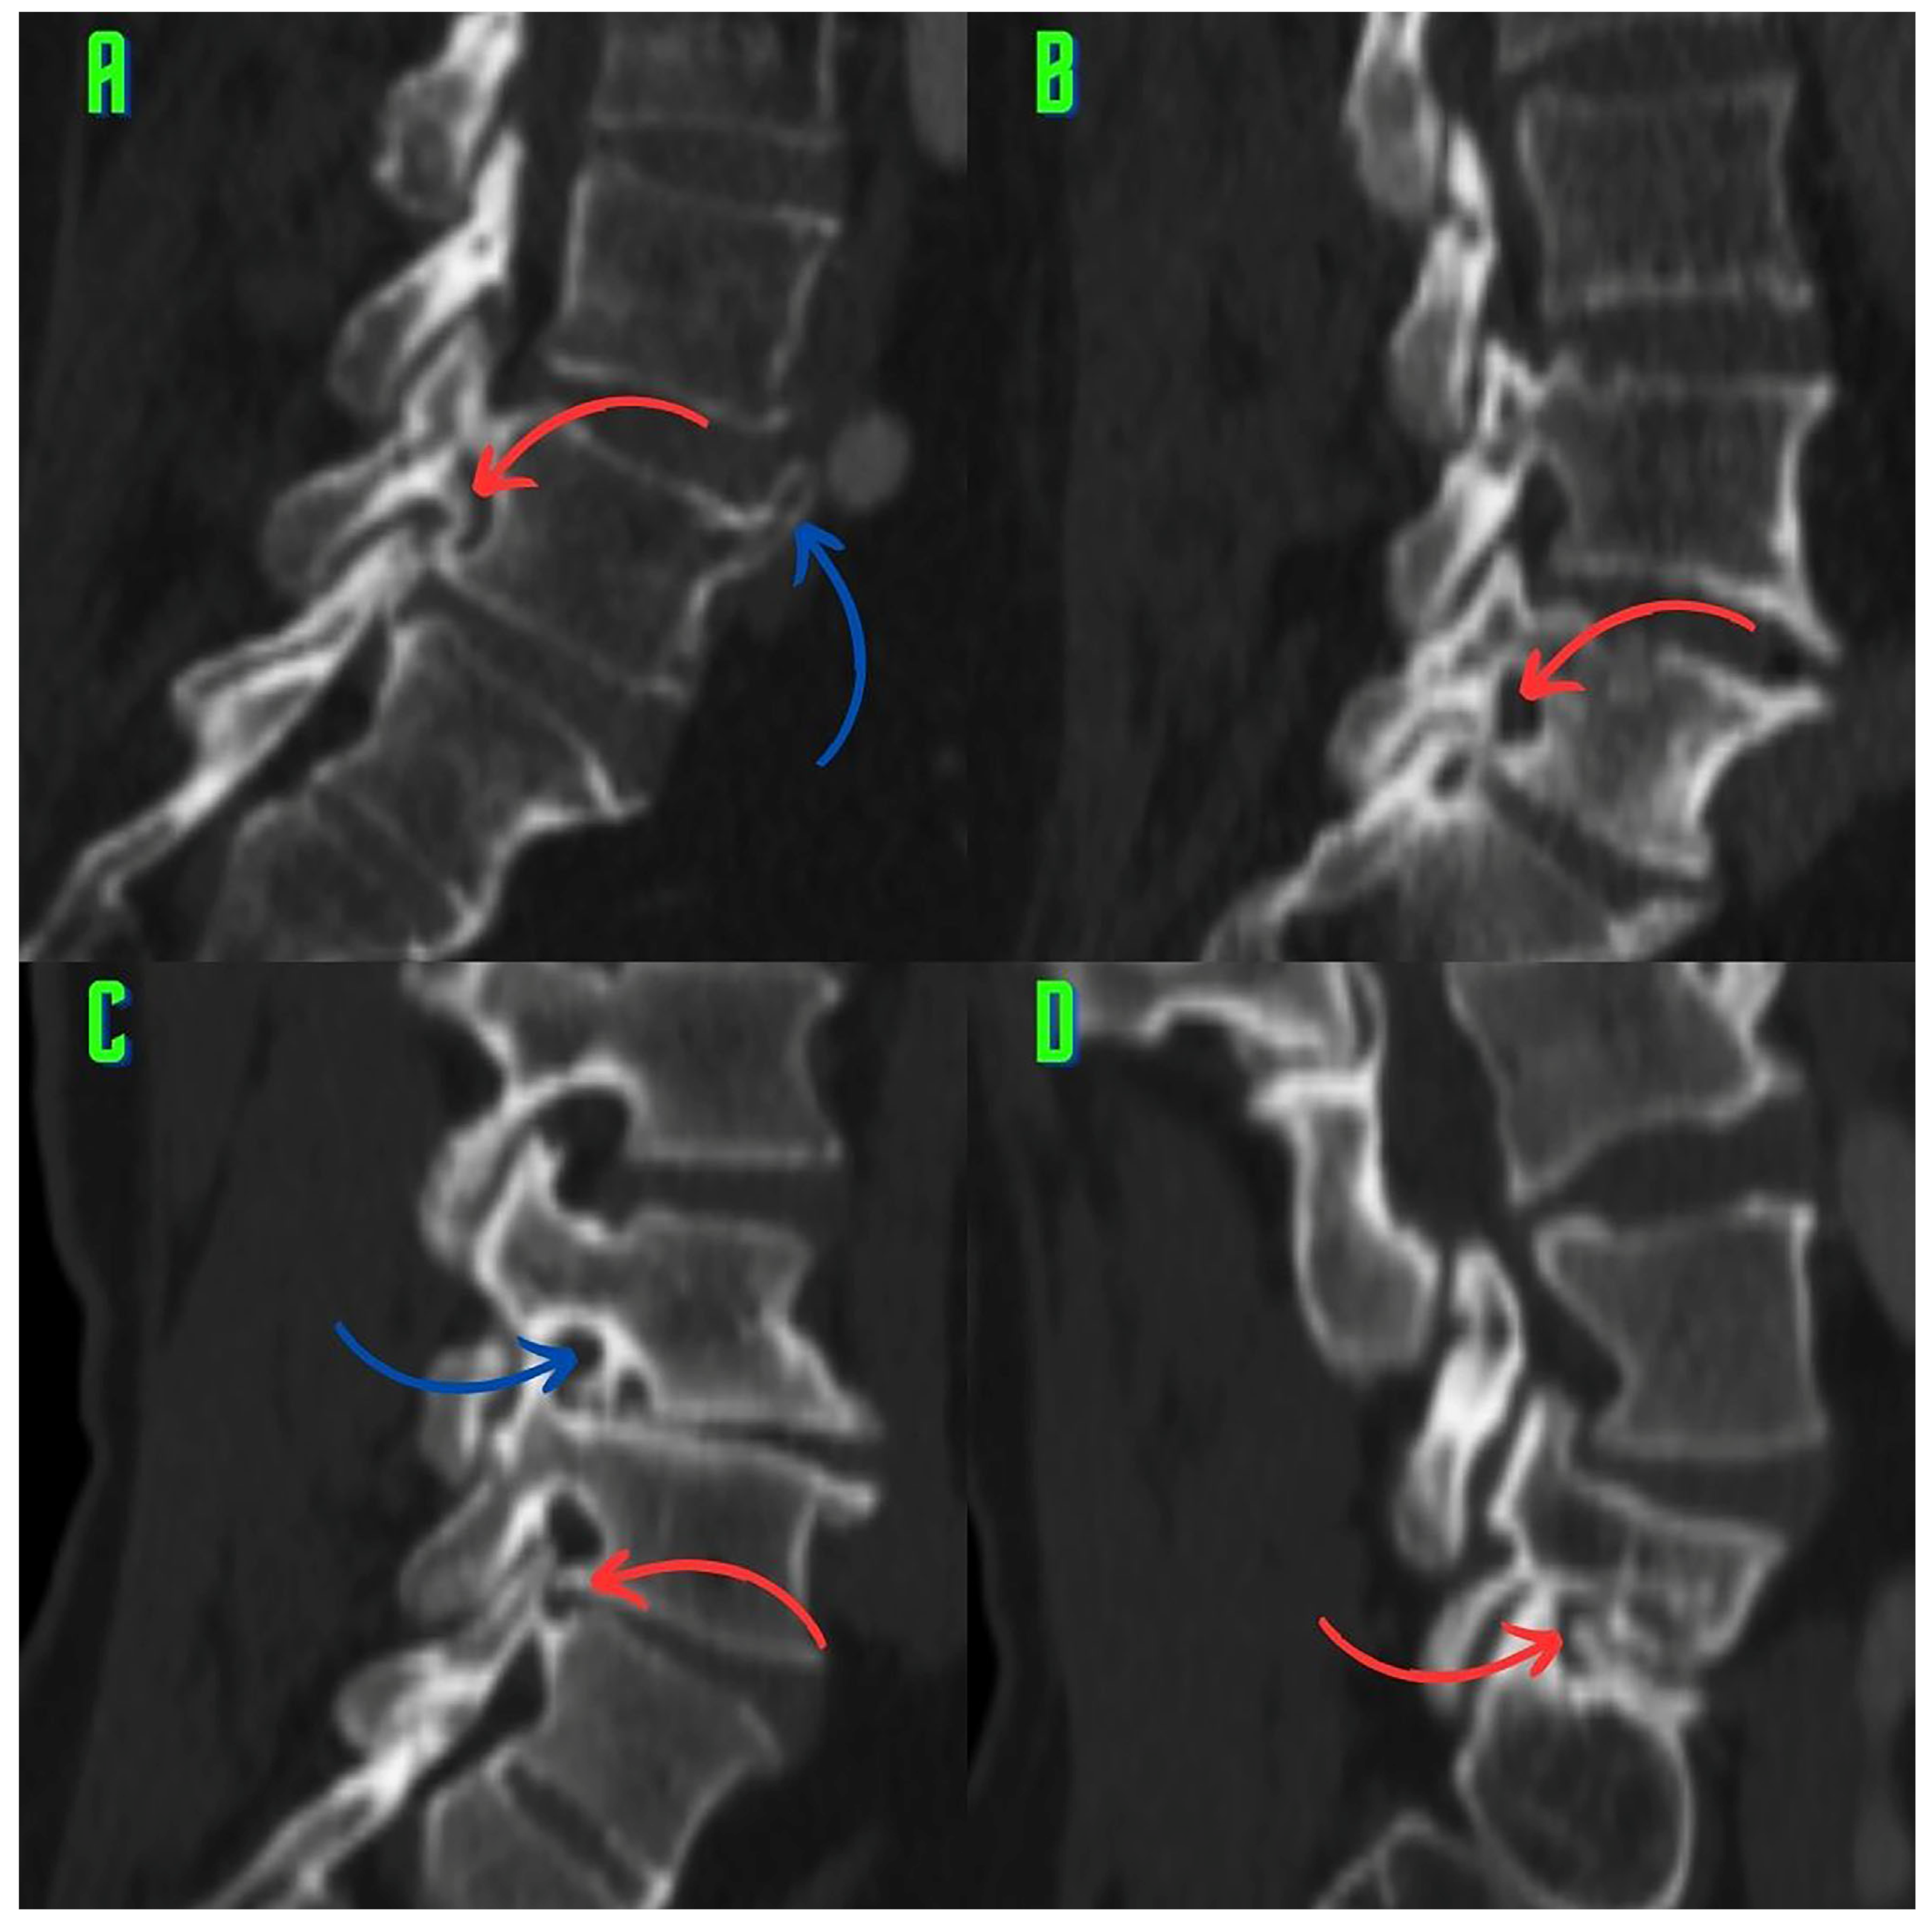

2.3. Image Analysis and Research Methods

3. Results

4. Discussion